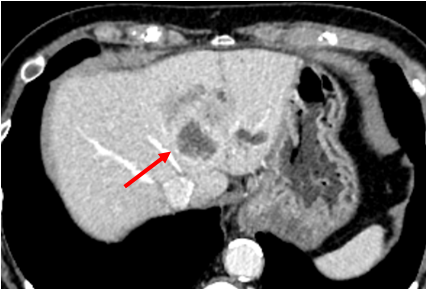

CT示新辅助治疗前肿瘤情况

(箭头示肿瘤压迫肝中静脉)